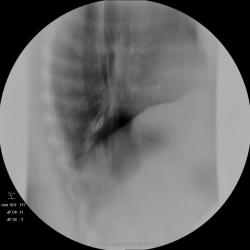

Женщина 50 лет поступила а пульмонологическо отделение с клиникой и диагнозом обострения бронхита. 15 лет назад перенесла тяжелую пневмонию нижней доли правого легкого. после этого находили выше указанные изменения в легих и наблюдали у фтизиатров. со слов " дисковидная туберкулема" или что-то вроде этого. на флю - картина на протяжении всего времени стабильная. на фбс - нижнедолевой бронх для эндоскопа не проходим, контактная кровоточивость, взята биопсия. прошу совета. какие будут мнения? выставляю только томо - снимки обычные не снимал. но картина на них подобная. по анализам без особенностей. не худела...

так как обозвать эту линзу с плотностью кальцинта? я вижу ателектаз-гиповентиляцию нижней доли, на фоне чего - эта "линза" - постпнемонический фиброателектаз?

А это не может оказаться обычным бронхолитиазом?

Мне очень импонирует мысль о БРОНХОЛИТИАЗЕ....